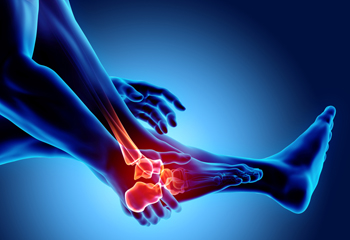

Finding Relief for Foot Arthritis

Arthritis is a form of joint inflammation that can find its way into the feet, bringing discomfort and challenges to mobility. Osteoarthritis, often linked to wear and tear, can lead to pain and stiffness in the foot's joints. Rheumatoid arthritis, an autoimmune disorder, can cause painful swelling and deformities. Gout, characterized by sudden, intense pain, emerges from uric acid buildup. Relief options encompass a range of strategies. Wearing custom orthotics, which offer cushioning and support, can help to reduce pressure on affected areas. Stretches and exercises can enhance flexibility and strength. Medications, including anti-inflammatories, can be beneficial in providing relief. Lifestyle adjustments, such as weight management and choosing proper footwear, can also alleviate symptoms. Consulting a podiatrist ensures a tailored approach to managing arthritis in the feet. If you have any type of foot arthritis, it is suggested that you contact this type of doctor who can offer you effective relief options.

Arthritis can be a difficult condition to live with. If you are seeking treatment, contact Jeffrey Radack, DPM from Texas Regional Foot & Ankle Clinics. Our doctor can provide the care you need to keep you pain-free and on your feet.

Arthritic Foot Care

Arthritis is a term that is commonly used to describe joint pain. The condition itself can occur to anyone of any age, race, or gender, and there are over 100 types of it. Nevertheless, arthritis is more commonly found in women compared to men, and it is also more prevalent in those who are overweight. The causes of arthritis vary depending on which type of arthritis you have. Osteoarthritis for example, is often caused by injury, while rheumatoid arthritis is caused by a misdirected immune system.

Symptoms

- Swelling

- Pain

- Stiffness

- Decreased Range of Motion

Arthritic symptoms range in severity, and they may come and go. Some symptoms stay the same for several years but could potentially get worse with time. Severe cases of arthritis can prevent its sufferers from performing daily activities and make walking difficult.

Risk Factors

- Occupation – Occupations requiring repetitive knee movements have been linked to osteoarthritis

- Obesity – Excess weight can contribute to osteoarthritis development

- Infection – Microbial agents can infect the joints and trigger arthritis

- Joint Injuries – Damage to joints may lead to osteoarthritis

- Age – Risk increases with age

- Gender –Most types are more common in women

- Genetics – Arthritis can be hereditary

If you suspect your arthritis is affecting your feet, it is crucial that you see a podiatrist immediately. Your doctor will be able to address your specific case and help you decide which treatment method is best for you.

How to Care for Your Arthritic Foot

Arthritis is an inflammation of the joints and it can occur at any joint in the body, especially in the foot. It generally effects those who are older, however, it can occur at any age. Although there are many different forms of arthritis, there are three main types that occur in the foot. The three types are osteoarthritis, rheumatoid arthritis, and gout.

The primary cause of osteoarthritis is aging. As you age, cartilage degenerates around the joints which causes friction and pain. Obesity can cause osteoarthritis through mechanical stress. Injuries that damage joints can increase the probability as well. Finally, a family history of osteoarthritis can also increase chances of having it.

Rheumatoid arthritis occurs when the immune system attacks the joint linings and weakens them over a long time. While there is no known cause of rheumatoid arthritis, obesity and smoking can increase your chances of getting it. Women are also more likely to get it than men.

Gout is a form of arthritis that occurs when there is too much uric acid in your blood and painful crystals form in your joints. Men are more likely to have gout than women. People who are obese or drink alcohol often are also more likely to develop gout. Furthermore, having diabetes, heart disease, high blood pressure, high cholesterol, gastric bypass surgery or a family history of gout may increase your likelihood of developing the condition.

Symptoms of arthritis include pain, stiffness, swelling in the joints. These symptoms can make it harder and more painful to walk. Physical activity can increase pain and discomfort. Furthermore, joint pain can worsen throughout the day for osteoarthritis. Gout attacks generally last several days with the first few being the worst.

Diagnosis of gout includes either a joint fluid test or a blood test. X-ray imaging can detect osteoarthritis but not gout. On the other hand, there is no blood test for osteoarthritis. Rheumatoid arthritis is difficult to diagnosis. Doctors utilize family and personal medical history, a physical examination, and antibody blood tests to determine if you have rheumatoid arthritis.

Treatment varies for the different kinds of arthritis. Anti-inflammatory medication or steroids can help reduce pain from inflammation of the joints. Changing shoe types can help with some symptoms. Wider shoes can help with discomfort from gout and osteoarthritis. High heels should be avoided. Shoes with proper arch support and that take pressure off the ball of the foot can help with rheumatoid arthritis. Drinking lots of water can also help rid uric acid from the blood. Losing weight, improving your diet, and limiting alcohol and smoking can also help prevent or lessen the symptoms of arthritis.

If you are having trouble walking or pain in your feet, see a podiatrist to check if you have arthritis.

Arthritis Can Cause Pain in the Feet and Ankles